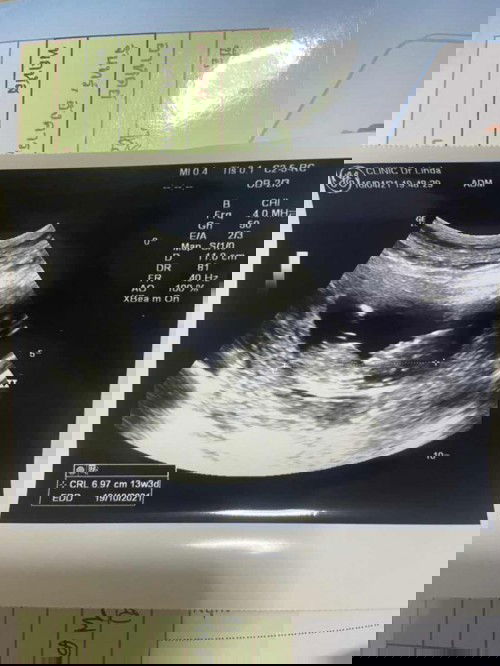

13w3d เห็นตะจู๋ 😊

13w3d คุณป้าหมอ บอก เห็นตะจู๋น้องด้วยแหละ 😊 #น้องชายคนสุดท้อง #คุณแม่ลูก3 🥰